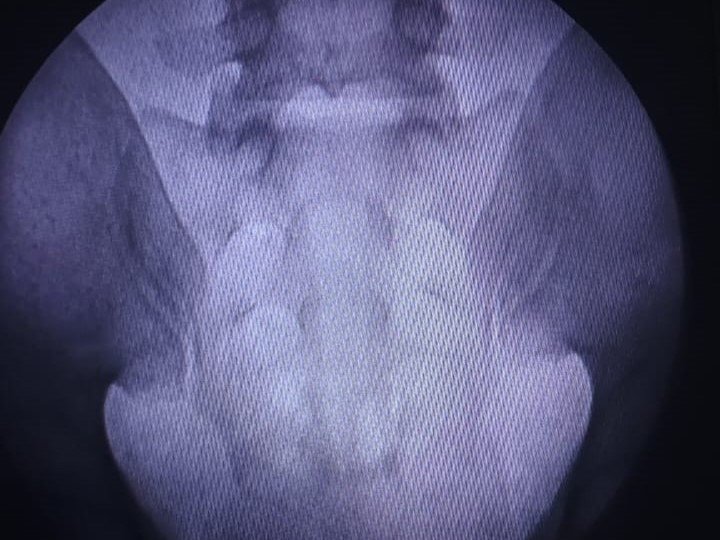

S1 - Selective Nerve Root Block